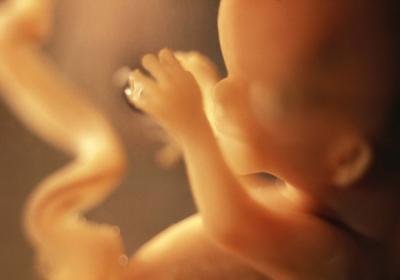

Одиннадцатая неделя беременности делает эмбрион плодом, он все больше становится похожим на человечка. Состояние беременной женщины в это время более или менее нормализуется. Но, все же, существует, кокая-то